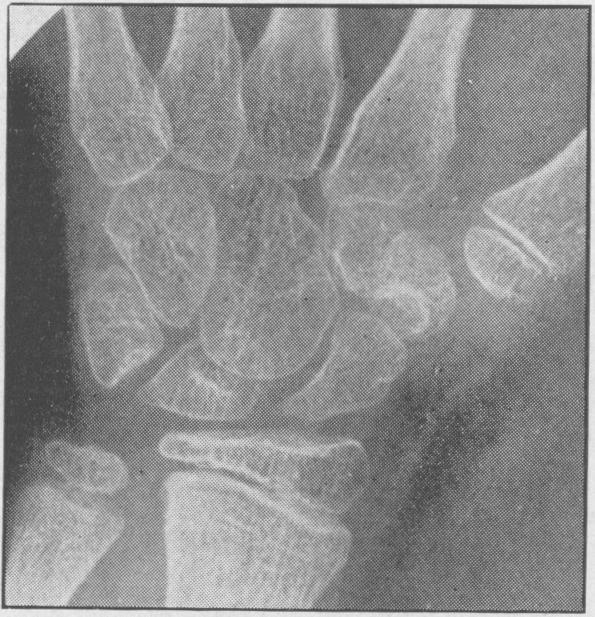

Juvenile rheumatoid arthritis (Still's disease).